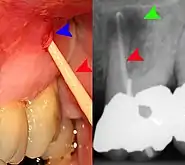

Clinical & xray correlation of pericoronitis

clinical shot of pericoronitis

An operculum (green arrow) over a partially erupted lower left third molar tooth. There is minimal inflammation and recurrent swelling.

xray of pericoronitis

A radiograph of the above tooth showing chronic pericoronitis, operculum (blue arrow) and bone destruction (red arrow) from chronic inflammation. Tooth is slightly disto-angular.